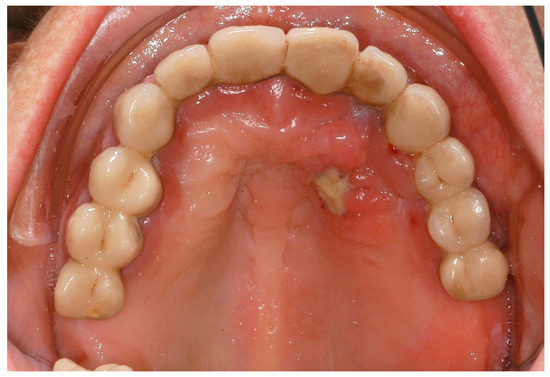

| Hypoplasminogenemia L90.5 | Periodontitis, gingival enlargement | exact pathomechanism unknown [85] | PLG 6q26 [41] | systemic diseases and conditions that affect the periodontal attachment apparatus: diseases affecting the oral mucosa and gingival tissue |